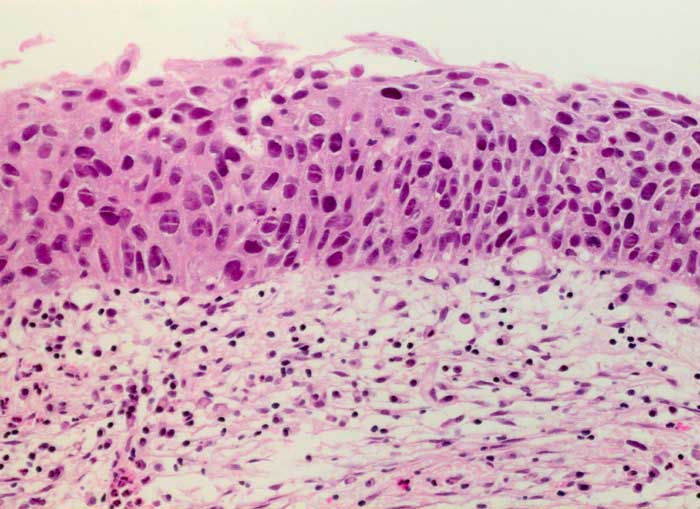

HSIL: schwere Dysplasie des Plattenepithels

Die am wenigsten differenzierten Zellen der schweren Dysplasie entsprechen dem Basalzelltyp. Die Kerne sind grösser als bei der mässigen Dysplasie. Da die Zellen gleichzeitig kleiner sind, erhöht sich die Kern-Zytoplasma Relation deutlich zu Gunsten der Kerne. Die vergrösserten Chromatingranula sind durch bandförmige Chromatinverklumpungen miteinander verbunden. Dadurch entsteht ein typisches Siebmuster. Die Kernmembran ist unregelmässig verdickt und zeigt häufig auch tiefere Einkerbungen.